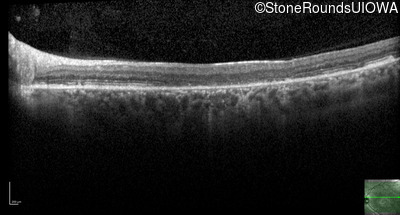

AR Stargardt Disease (IIA)

Age at visit: 42 years

AR Stargardt Disease ABCA4 Val256Val GTG>GTT Gly1961Glu GGA>GAA AR